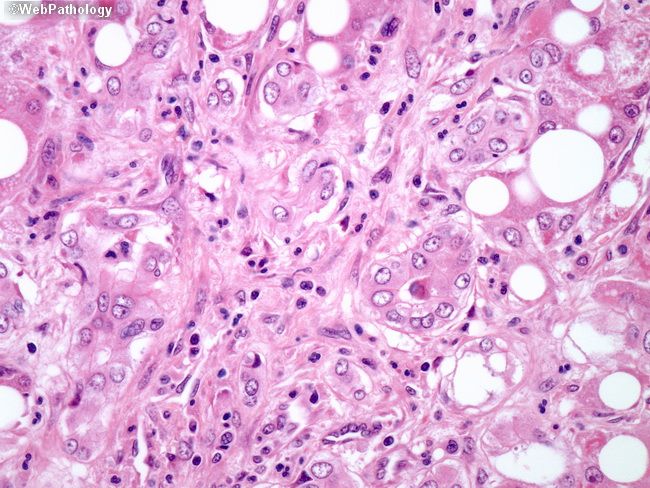

Фото Липосаркомы Мягких 114 фото